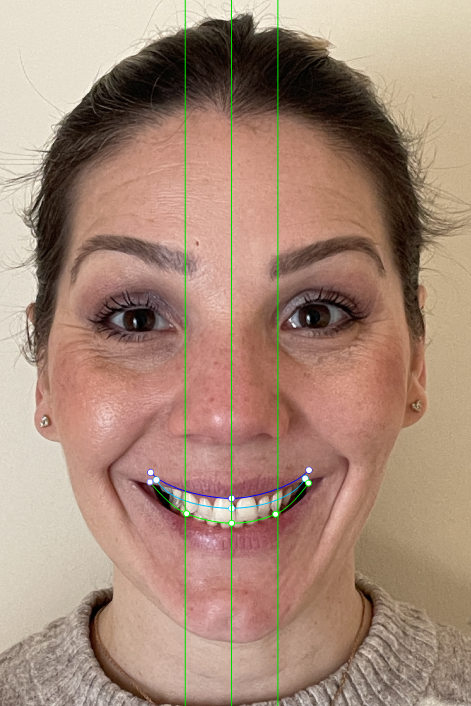

Elevantia Solutions accepted the challenge by designing a treatment plan with Ortho Root Plan Design, a tool that allows orthodontic planning based on the exact position and movement of roots during treatment. This is essential for complex cases because it reduces risks, prevents root damage, and ensures maximum predictability

Ortho Movements

The proposed design corrected midline discrepancies, improved occlusion, and established the foundation for future restorative work. Thanks to this advanced approach, the treatment was safer, more conservative, and highly predictable, providing security for the doctor and confidence for the patient